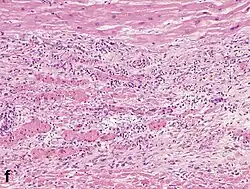

Under the microscope, myocardial infarction presents as a circumscribed area of ischemic, coagulative necrosis (cell death). On gross examination, the infarct is not identifiable within the first 12 hours.[22]

Although earlier changes can be discerned using electron microscopy, one of the earliest changes under a normal microscope are so-called wavy fibers.[23] Subsequently, the myocyte cytoplasm becomes more eosinophilic (pink) and the cells lose their transversal striations, with typical changes and eventually loss of the cell nucleus.[24] The interstitium at the margin of the infarcted area is initially infiltrated with neutrophils, then with lymphocytes and macrophages, who phagocytose ("eat") the myocyte debris. The necrotic area is surrounded and progressively invaded by granulation tissue, which will replace the infarct with a fibrous (collagenous) scar (which are typical steps in wound healing). The interstitial space (the space between cells outside of blood vessels) may be infiltrated with red blood cells.[22]

| Neutrophil infiltration | 12–24 h | 1–3 days | 5–7 days |

| Macrophages and lymphocytes | 3–5 days | 5–10 days (including 'siderophages') | 10 days to 2 months |

| Fibroblast and young collagen* | 5–10 days | 2–4 weeks | After 4 weeks; depends on size of infarction; |

| Dense fibrosis | 4 weeks | 2–3 months | No |

Differential diagnoses for myocardial fibrosis:

- Interstitial fibrosis, which is nonspecific, having been described in congestive heart failure, hypertension, and normal aging.[27]

- Subepicardial fibrosis, which is associated with non-infarction diagnoses such as myocarditis[28] and non-ischemic cardiomyopathy.[29]